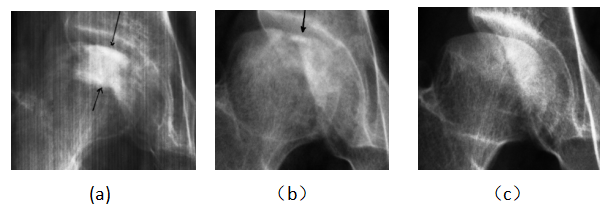

病例1女,51岁,患病4年,治疗12个月后痊愈。治疗前,股骨头顶部呈V形缺损,边界和骨密度不均匀(a)。治疗8个月后,坏死面积变小,骨密度降低,密度均匀(b)。股骨头表面光滑,坏死区消失,可见恢复过程的低密度区(c)

Case 1 female, 51 years old, 4 years old, recovered after 12 months of eating. Before eating, the top of the femoral head was V-shaped defect, with uneven boundary and bone density (a). After 8 months of consumption, the necrotic area became smaller and the bone density decreased, but it was more uniform (b). After eating, the head was smooth, the necrosis area disappeared, and the low density area (c) of the recovery process could be seen